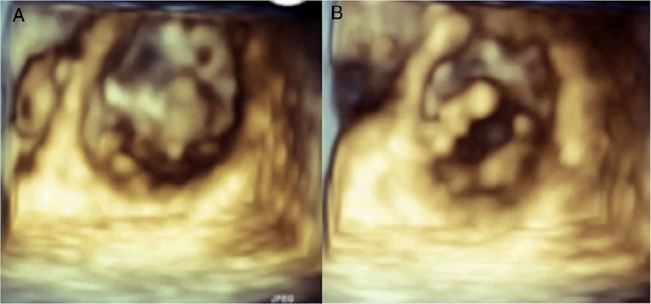

MLG is a female 58 years old with a history of rheumatoid arthritis diagnosed in December 2011 based on elevated rheumatoid factor, erythrocyte sedimentation rate and C-reactive protein, the presence of anticyclic citrullinated peptide antibody (anti-CCP), and bony erosions in the hands. She initially received treatment with immunosuppressors (methotrexate) and later with biological (abatacept) therapy with improvement and remission of the disease. She presented to the emergency room of our institution with a 3 weeks-history of a progressive dyspnea from great to moderate efforts, palpitations, fever (38.8 ◦C), malaise, dry cough and headache. On examination, she was tachycardic (HR: 101/min), with oxygen desaturation (P02 = 70%) and had bibasilar lung rales. The laboratory analysis showed leukocytosis (21.4 × 103/m3) and mild anemia (Hb – 12.7 g/dL and Htc – 40%). Blood cultures were negative. The chest computed tomography showed areas of bilateral alveolar occupation in relation to acute inflammatory process without pleural effusion. The transthoracic bidimensional (Fig. 1A–F) and three-dimensional echocardiogram revealed nodular thickening on the both mitral leaflets and in the subvalvular apparatus of the mitral valve without mitral regurgitation (Fig. 2A and B), small nodules in the aortic leaflets (Fig. 3A and prominent nodules on the tricuspid valve with mild tricuspid regurgitation (Fig. 3B), mild pulmonary hypertension, left ventricular diastolic dysfunction type I and normal left ventricular systolic function. The patient was treated with intravenous steroids and broad spectrum antibiotics with clinical improvement, but without changes in the valvular lesions. Actually she is in NYHA functional class I and the chest radiograph after the resolution of infectious process showed interstitial lung bilateral thickening and reticulonodular parahiliar and basal pattern, the left cardiac profile is abnormal and the aorta unrolled (Fig. 4).

Figure 2 Transthoracic three-dimensional image of ventricular view of mitral valve in sistole (A) and diastole (B), showing nodular thickening in both leaflets.

Actually, three-dimensional echocardiography has been conceived as one of the most promising methods for the diagnosis and follow-up of valvular heart disease. In particular, for mitral valve diseases, this new approach has proven to be the most unique, powerful, and convincing method for understanding the complicated anatomy and dynamism of the mitral valve and also of the other cardiac valves.11 This technique should be performed in RA, because the resolution of the nodules is very clear as we observed in our patient. It has been shown that untreated systole in patients with RA is an important problem and joint efforts of rheumatologists and cardiologists may help to improve the cardiovascular morbidity and mortality in RA.5,8